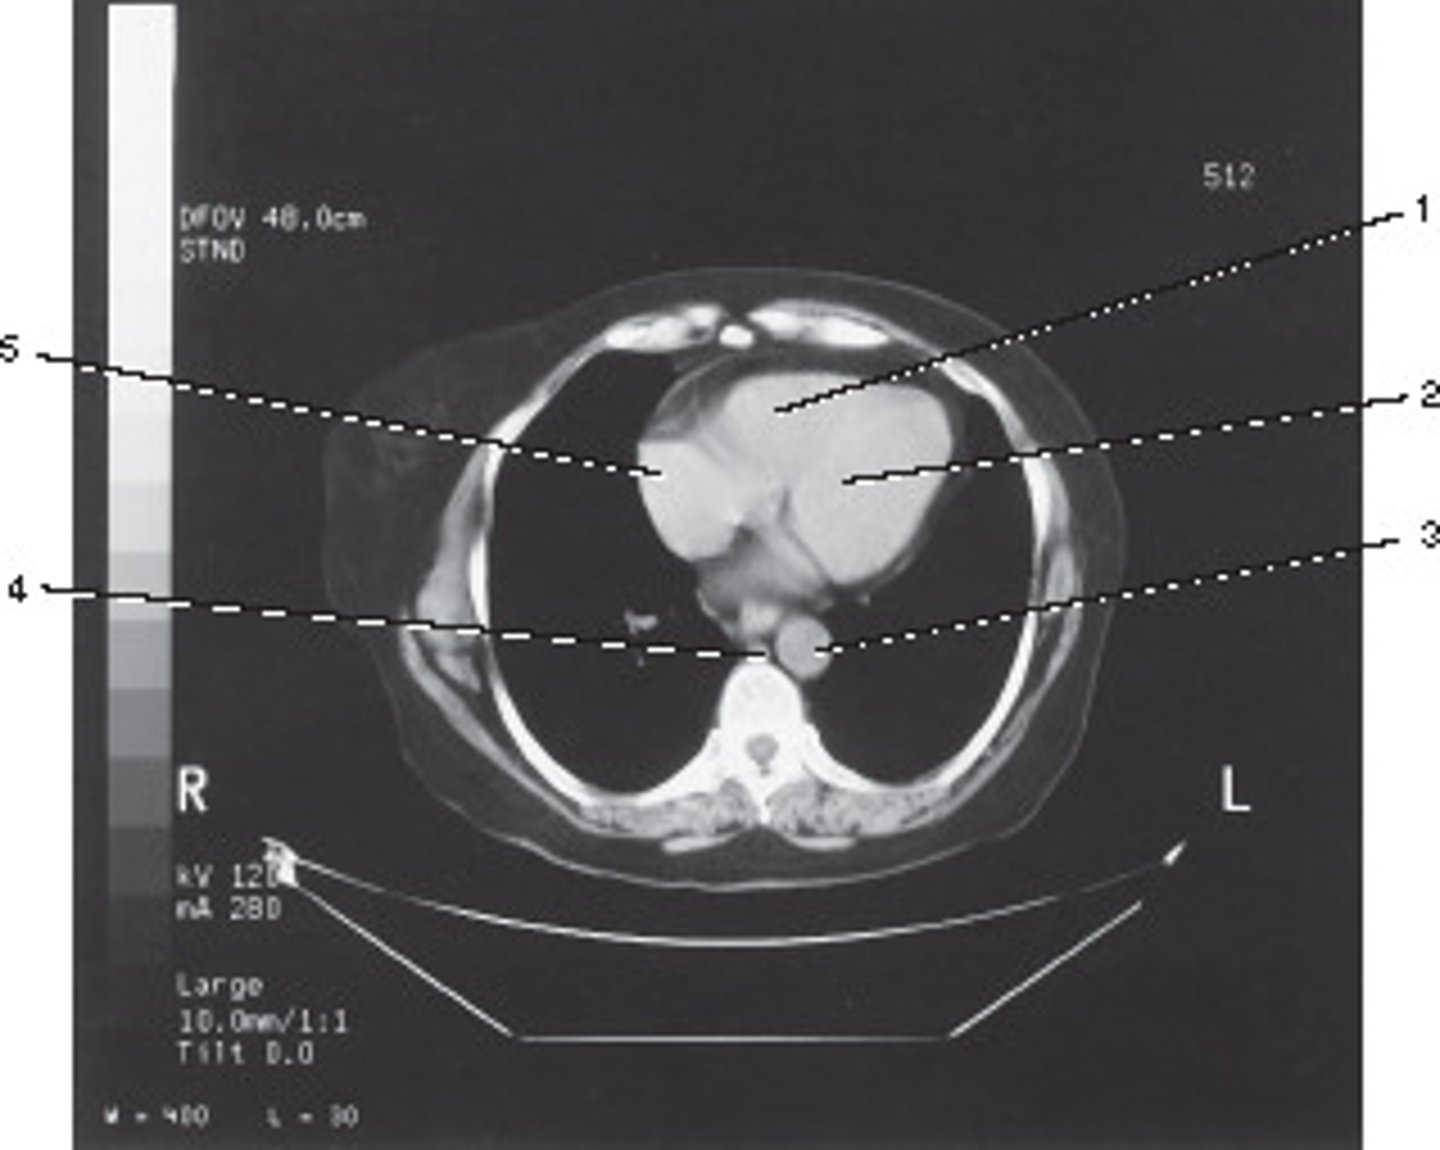

standard, 512, and 10.0 mm

What algorithm, matrix size, and section thickness were used for this image?

<p>What algorithm, matrix size, and section thickness were used for this image?</p>

Which number corresponds with the right atrium?

<p>Which number corresponds with the right atrium?</p>

Azygous Vein

Number 4 corresponds to which of the following?

<p>Number 4 corresponds to which of the following?</p>

Descending Aorta

Number 1 corresponds to which of the following?

<p>Number 1 corresponds to which of the following?</p>